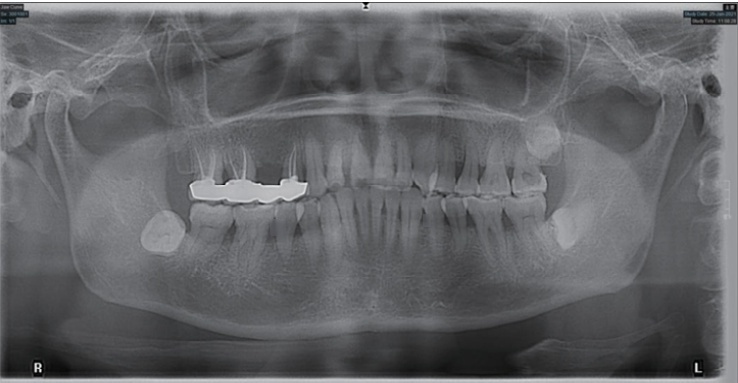

显微根尖手术联合引导组织再生术治疗左上前牙根尖囊肿1例及3年回访

病史摘要:43岁女性,因“左上前牙牙松动”就诊,左上前牙曾在外院行根管治疗,时间不详。否认心血管疾病、糖尿病等系统性疾病史,否认肝炎等传染性疾病、药物过敏及精神和心理病史。口腔卫生差。诊疗过程:口腔检查发现多颗牙齿存在不同程度的问题。根尖片和CBCT显示21、22根尖周有大面积阴影等情况。诊断为12继发龋、21和22慢性根尖周炎。治疗方案包括12充填治疗,21显微根管治疗,22显微